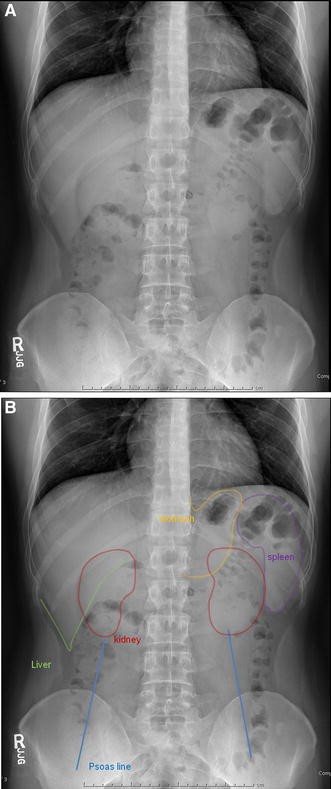

Extends to the hemidiaphragm; Although ultrasound and CT are more informative means of imaging the solid organs of the abdomen, occasionally you will see evidence of enlarged organs on an abdominal Xray Hepatomegaly Hover on/off image to show/hide findingsTalk to our Chatbot to narrow down your search

Hepatomegaly & Transient Hepatomegaly & XRay Abnormal Symptom Checker Possible causes include Hepatopathy Check the full list of possible causes and conditions now!Talk to our Chatbot to narrow down your searchAssessment of liver size is commonly made on ultrasound or CT, although gross hepatomegaly may be apparent on abdominal radiograph For the adult liver midclavicular line averages cm in craniocaudal length 2 a liver that is longer than cm in the midclavicular line (MCL) is considered enlarged

Psoas muscle symmetrical triangles either side of the lumbar spine Hepatomegaly can represent intrinsic liver disease or may be the presenting physical finding of a generalized disorder Early diagnosis and treatment of children who have liver disease is important because specific treatments are available for some diseases that can prevent disease progression or hepatic failureHepatomegaly is another word to describe this problem If both the liver and spleen are enlarged, it is called hepatosplenomegaly Abdominal xray;

Hepatomegaly is the condition of having an enlarged liver It is a nonspecific medical sign having many causes, which can broadly be broken down into infection, hepatic tumours, or metabolic disorder Often, hepatomegaly will present as an abdominal mass Depending on the cause, it may sometimes present along with jaundiceHepatomegaly (abdominal xray) Case contributed by Dr Jeremy Jones Diagnosis probable Diagnosis probable From the case Hepatomegaly (abdominal xray) Xray Loading Stack 0 images remainingSplenomegaly is a subjective radiograph finding as there are no reliable objective criteria;